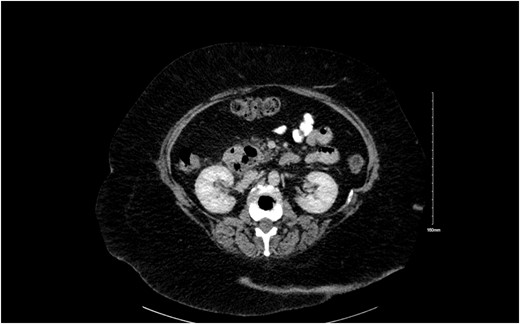

We present a case of a 70 year old female who presented in emergency department with a 3 day history of constant abdominal pain in epigastrium and subsequent migrating to right upper quadrant (RUQ) with nausea, anorexia, and jaundice. Her background history was significant for laparoscopic cholecystectomy (1994), right mastectomy and SLNB: IDC T2N0M0 grade 2 (2013), lararoscopic adhesiolysis (SBO; 2014) and hypertension. Her general physical examination revealed an obese lady with BMI of 33, mild scleral icterus, RUQ tenderness with negative Murphy’s sign. Her inital labs were Hb 12.7, WBC 14.3, CRP 160, amylase 51, lactate 1.1, liver function tests Tot. Bil 58.5, Direct 52.9, alkaline phosphatase (ALP) 167, gamma-glutamyl transferase (GGT) 221, and alanine transaminase (ALT) 99. These blood tests were followed by an ultrasound GB which showed no biliary dilatation. We booked an magnetic resonance cholangiopancreatography (MRCP) which also showed no evidence of choledocholithiasis. Dilatation of common bile duct (CBD) measuring 12 mm, pancreas is poorly visualized, low signals at pancreatic head- suggesting a CT AP for clarification. CT AP showed a low signal adjacent to pancreatic head representing a large duodenal diverticulum with resolved intra-and extra-hepatic biliary dilatation highlighted on MRCP and a normal CBD (Fig. 1).